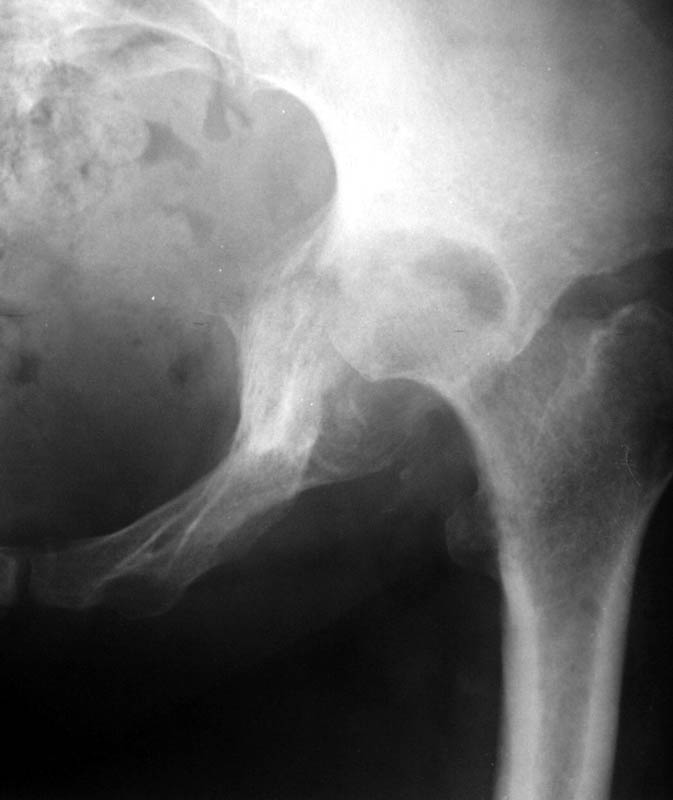

Женщина, 45 лет. В марте перенесла левосторонний коксит неизвестной этиологии. Специфику и онкологию исключили.

Интраартикулярных инъекций не было. Сейчас процесс клинически и рентгенологически - стабилизировался. Состояние вполне удовлетворительное.Предполагается тотальное эндопротезирование с пластикой полости аутокостью. Возможна ли бесцементная <чашка>? Заранее благодарю! С уважением,А.В.Владзимирский

Дополнение - проконсультировался с женой-она специалист рентгенолог - на КТ большое колиество мягкотканного компонента - ищите микоплазмы или бруцеллу. Я склоняюсь к виопсии.

Пртезирование через пол года после коксита закончившегося лизисом сустава, который на снимках выглядит как гнойный? Что значит неизвестной этиологии?

Уважаемый коллега! Последняя версия - мы пролистали ренгенологическую книженцию-так картинка вполне подходит под сустав Шарко (neuropatic joint ). В тазобедренном суставе патология редкая (но меткая). Ищите причину - варианты - нейросифилис, сирингомиелия, опухи спинного мозга (и выше тоже) компрессия спинного

мозга извне, рассеяный склероз, алкоголизм. А так-же : склеродерма ,Рейно,ревматоидный артрит, амилоидная инфильтрация нервов,и это не считая всяких менингеомиелоцеле,asymbolia,Riley-Day syndrom,и все возможные другие нейропатии. На данном этапе не спешите оперировать(протезирование протиопоказано при нейропатических суставах),проконсультируйтесь с классным невропатологом,сделайте МЯР головного озга и